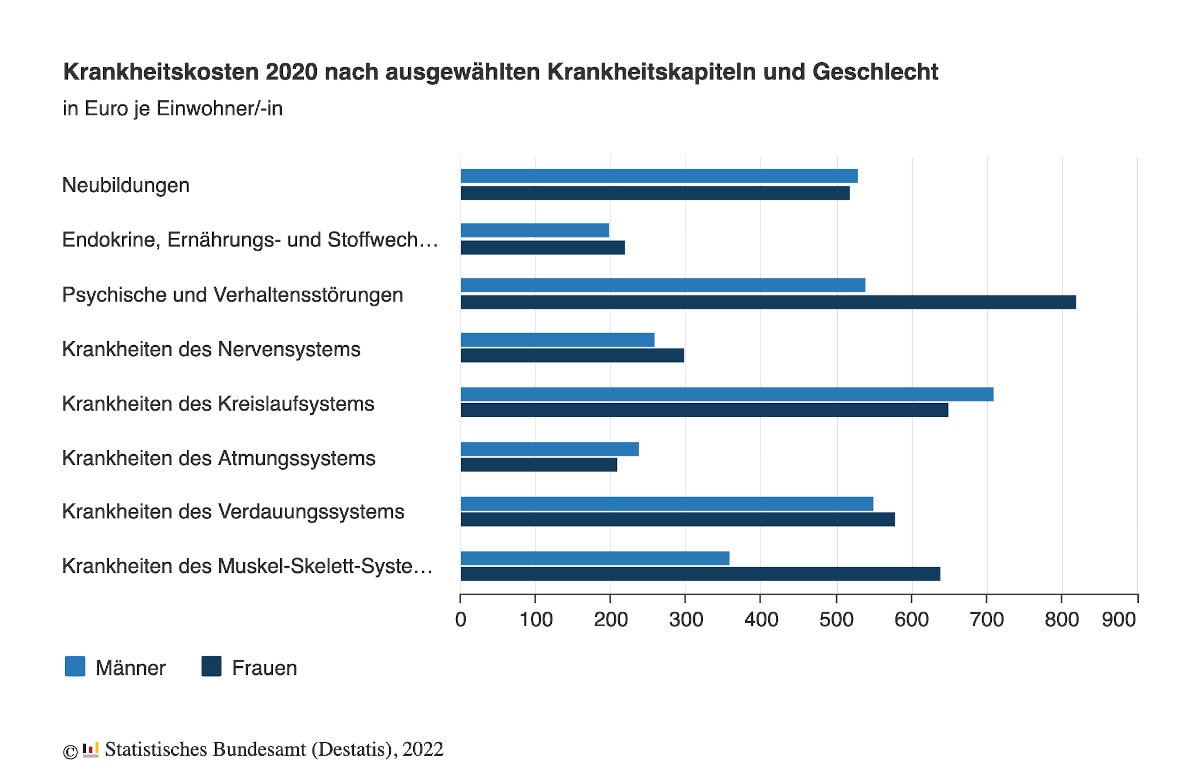

Gerade in Hinblick auf die Kategorien gibt es zwischen den Geschlechtern enorme Unterschiede – insbesondere bei der Psyche, Muskeln und Knochen. Die folgende Grafik zeigt sie: